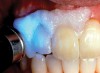

The whitening agents are available in various concentrations ranging from 10% carbamide peroxide (equal to 3.4% hydrogen peroxide) to 38% hydrogen peroxide. If the higher concentration agents contact the soft tissues, they can produce a chemical “burn” that turns the tissues temporarily white (Figure 1 and Figure 2). Although tissues quickly return to their normal color once they rehydrate, they may be mildly uncomfortable for a few hours. The patient may be distressed by the temporary appearance of the whitened soft tissues. A rubber dam or other protective barrier is mandatory to effectively seal off the tissues (Figure 3). In-office systems usually supply a light-cured resin in a syringe to apply around the cervical areas to confine the agent to the teeth (Figure 4 and Figure 5). In addition, flexible spreaders should be placed in the mouth to prevent the cheeks or lips from contacting the whitening agent.

Figure 1  Soft-tissue chemical burns near the left commissure of the mouth and along the free gingival margin due to exposure to the whitening agent.

Figure 2  Soft-tissue chemical burns near the left commissure of the mouth and along the free gingival margin due to exposure to the whitening agent.